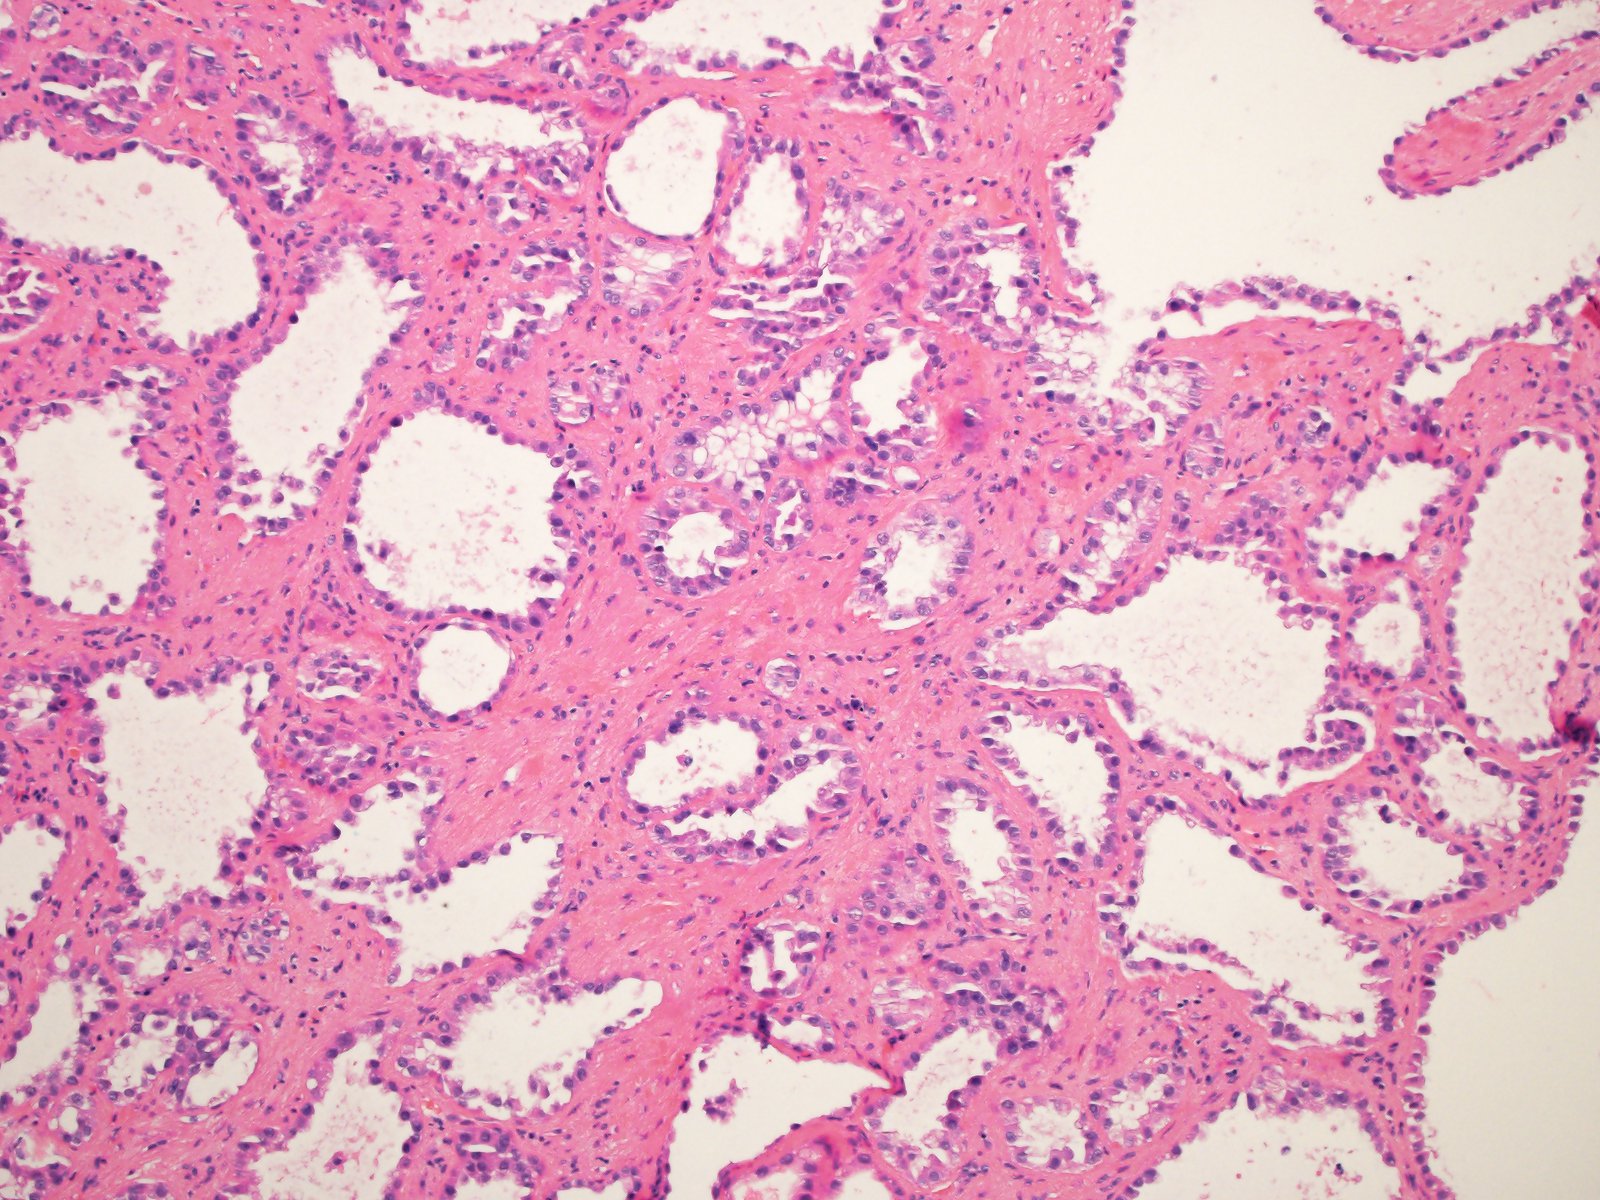

Classification of renal tumors

Case ID: 814